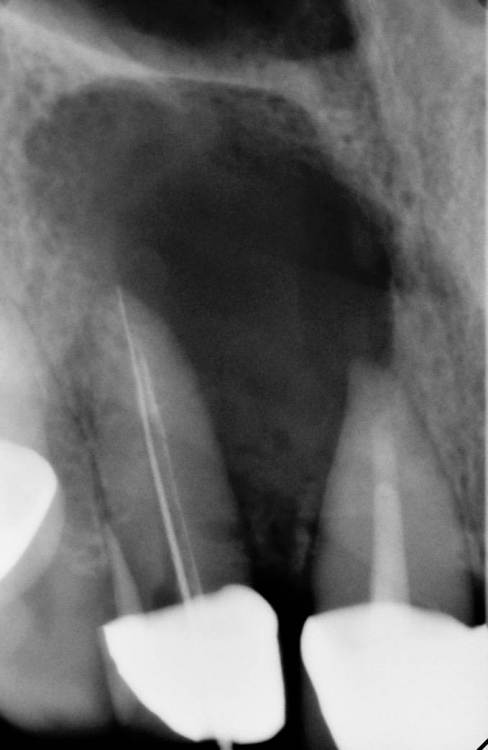

На КЛКТ прослеживается ороназальное  сообщение (его и на прицелках видно). Пациента ничего не беспокоит, функция и эстетика восстановлены

прослеживается ороназальное  сообщение

Как думаете, сообщение сразу было с момента  начал лечения? (кт диагностического не было?)

Было изначально